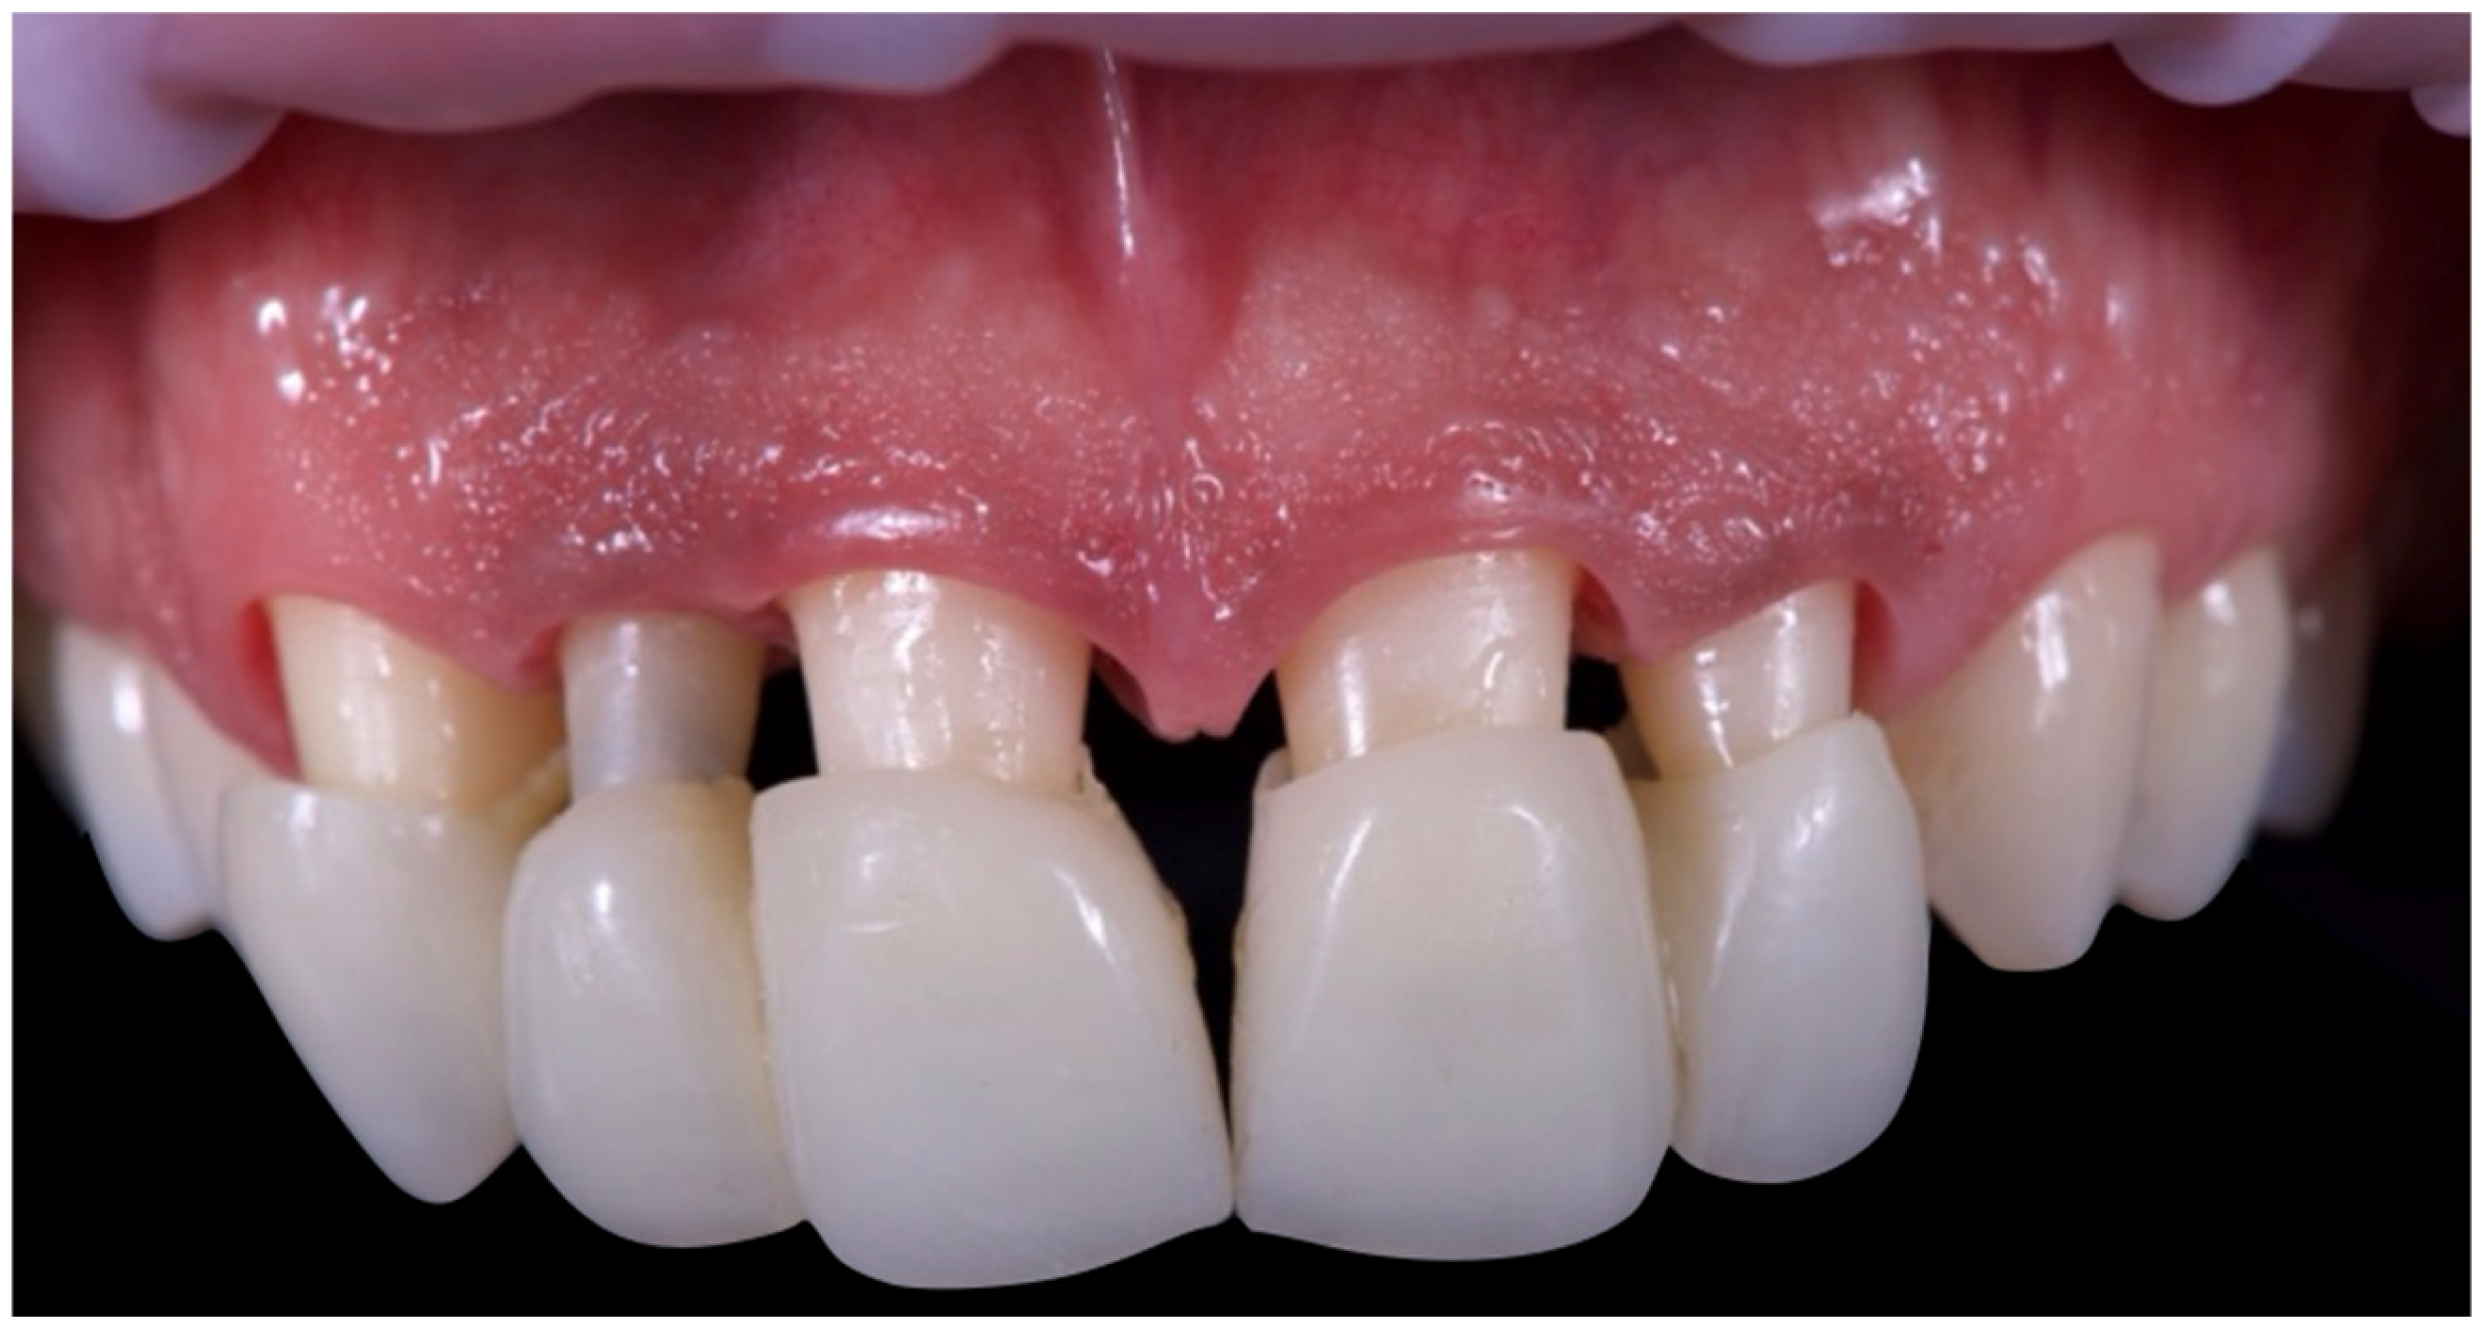

The first set of provisional restorations (Figure 10) was cemented using a non-eugenol temporary luting agent (Temp-Bond™ Clear, Kerr Dental, 8302 Kloten, Switzerland).

Figure 10. First provisional restoration.

These provisionals were segmented into two units (right and left) and maintained the existing interincisal diastema. The deep overbite was corrected, and an appropriate incisal guide was established. Both provisional restorations were progressively modified every 2–3 weeks to promote soft tissue adaptation, manage the emergence profile, and support the re-establishment of a new prosthetic cementoenamel junction (CEJ) over time. This approach also allowed for the continuous evaluation of the patient’s phonetics and functional dynamics. Approximately four months later, the preparations were refined under 16× magnification to optimise the emergence profiles and support soft tissue conditioning while preserving the edgeless finish line to enhance papillary stability and control (Figure 11).